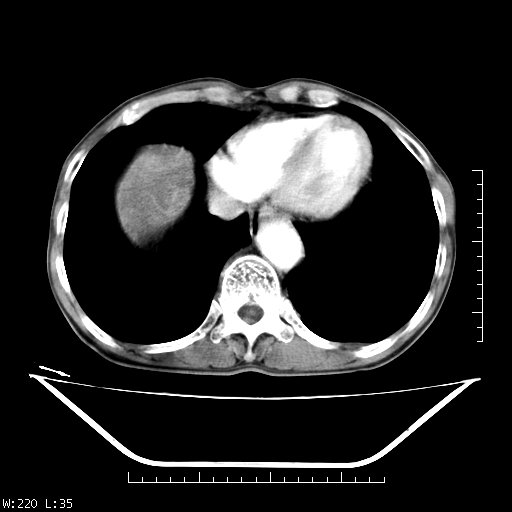

男,70,右上腹痛两月,有乙肝病史,b超提示肝占位,ct如下,请会诊。

补充:该患者afp9.24

肝右叶类圆型密度减低影,密度不均,边界清晰其内可见更低密度影,腹膜后可见小淋巴结肿大,增强扫描动脉期病灶明显强化,静脉期及延时扫描见强化不明显,快进快出表现。

1.肝右叶低密度影考虑为肝癌;

2.肝转移待除外。

平扫呈低密度占位,动脉期斑片状明显强化,病灶边缘清晰,见假包膜;门脉期呈低密度,符合肝癌快进快出强化特征

补充:该患者afp 9.24,似乎与原发性肝癌不符合,另胰头区结构正常吗?请大家继续发表高见。